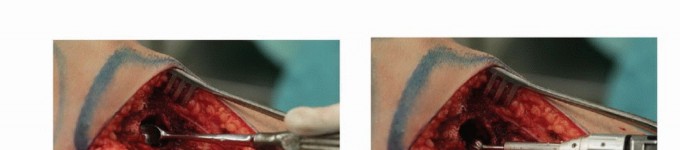

الكشط والعلاج المساعد (Curettage and Adjuvant Therapy):

تُستخدم عادة لأورام العظام الحميدة، حيث يتم كشط الورم من داخل العظم، ثم يتم استخدام مواد مساعدة مثل الفينول أو النيتروجين السائل أو الكي الكهربائي لتدمير أي خلايا ورمية متبقية.

يُعد العلاج بالتبريد، خاصةً بتقنية الصب المباشر بالنيتروجين السائل، ثورة حقيقية في علاج أورام العظام، حيث يقدم بديلاً فعالاً وآمنًا للجراحات الكبرى، مع الحفاظ على الطرف المصاب ووظيفته. يعتمد هذا النهج على تدمير الخلايا السرطانية عن طريق تعريضها لدرجات حرارة منخفضة جدًا، مما يؤدي إلى تجميدها وموتها.

تقنية الصب المباشر بالنيتروجين السائل: تفاصيل الإجراء

تعتبر تقنية الصب المباشر بالنيتروجين السائل (Direct Pouring Liquid Nitrogen Technique) في العلاج بالتبريد لأورام العظام من التقنيات المتقدمة التي تتطلب دقة عالية وخبرة جراحية متخصصة. يفضل الأستاذ الدكتور محمد هطيف هذه التقنية نظرًا لفعاليتها في تحقيق تجميد عميق وشامل للورم، مع الحفاظ على الأنسجة السليمة المحيطة.